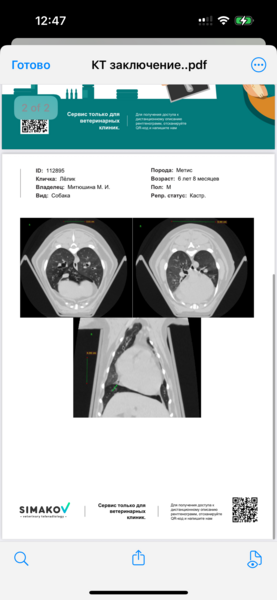

Для постановки диагноза и лечения необходимы КТ и бронхоскопия, так называемый БАЛ и обязательные анализы и обследования.  1 ноября  в Ветсити (чек и выписка прилагаются) было сделано КТ с контрастом и анализы.

Было потрачено 29 500 руб., силами неравнодушных людей было собрано - 21 000 руб. Нужно собрать еще 8 500 руб., чтобы закрыть долг. Но на этом расходы не заканчиваются, нужно сделать еще бронхоскопию под наркозом, посевы. Это еще около 15 000 руб. Сумма для нас неподъёмная.Пожалуйста, помогите Лёлику нормально дышать и жить!Сбор на карту Сбербанка 💳 СБ  4276380165516209Или Тинькофф 💳 2200700125863828 Светлана Васильевна  Н. с пометкой «Благотворительность Лёлик»